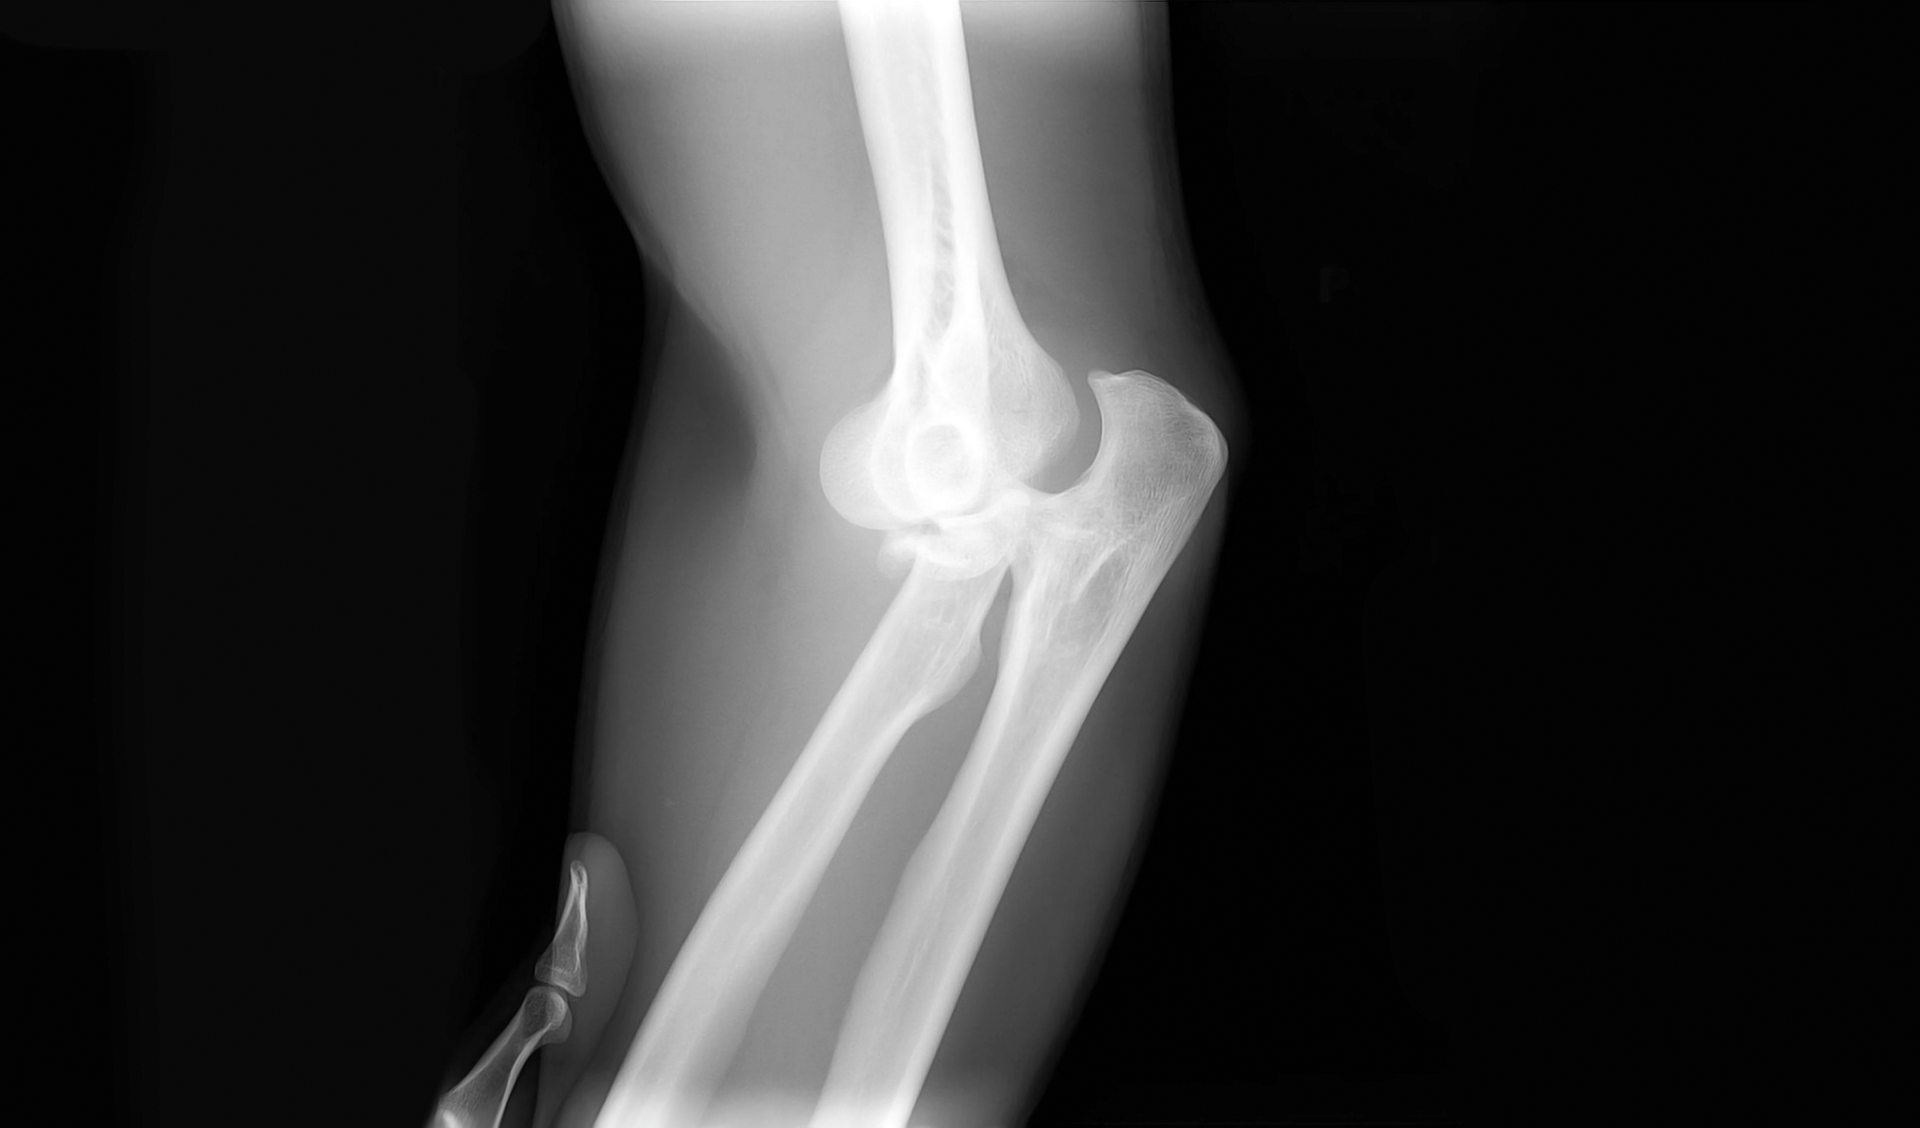

fracture | A fractured limb should be immobilized and the victim must immediately go or be taken to hospital. If there is a large swelling, a cold compress can be applied on the painful site. | In the case of open fractures, do not attempt to hide the protruding bone under the skin. Just rinse the wound with clean water and immediately call the ambulance service. |

sprain | A dislocated joint and adjacent bones should be immobilized and cooled down and then you should go to hospital, where a doctor will fix the dislocated joint and will put a dressing on it in a professional way. | Sprains that do not cause much pain or swelling do not require a visit to hospital. |